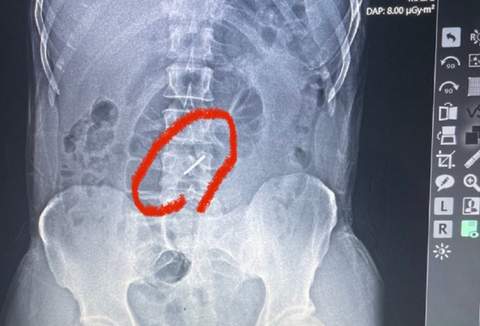

Його терміново направили на рентген, результати якого шокували медиків.

"При обстрілі елемент касетної бомби, так звана "стрілка", потрапила в ліве підребер'я, зламала два хребці в поперековому відділі хребта і застрягла в хребті", - розповідає лікар військово-польового госпіталю, Львівський Судинний хірург Тарас Кобза.

Уламки зламаних хребців могли пошкодити нерви і судини. Однак, на щастя, цього не сталося. Коли боєць йшов до польового шпиталю, він навіть не підозрював, що в хребті у нього - застрягла "стрілка" від касетної бомби.

Елемент ворожого боєприпасу зробив прокол шкіри всього на 1 мм, і захисник України навіть його не помітив - подумав, що це звичайна родимка.